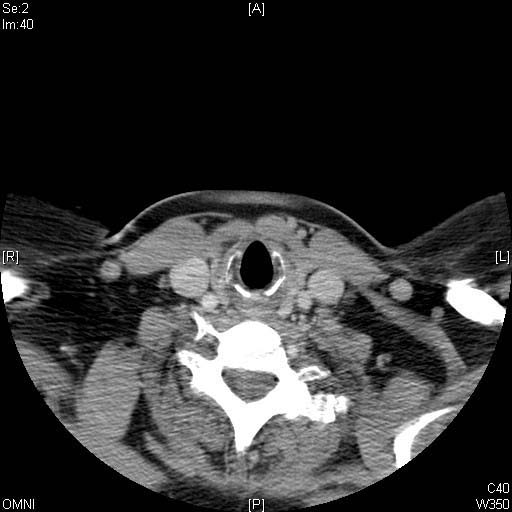

Identify Cricoid cartilage